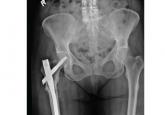

ArticleBisphosphonate-related atypical femoral fracture: Managing a rare but serious complicationAuthor:Susan Bukata, MDPublish date: November 1, 2018Concern about this rare complication has led to a decrease in bisphosphonate use.Read More